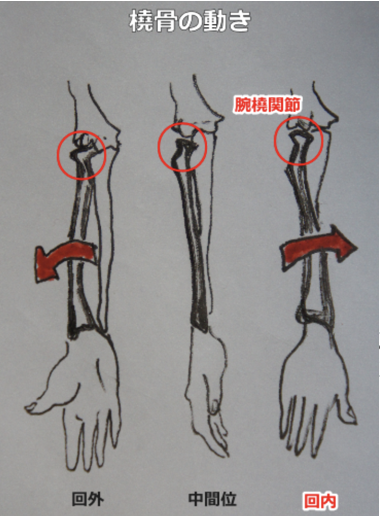

上記の状態なら、肘を直角に曲げた時点で橈骨は回内しています。

先ほどの動きをした時には、橈骨頭は回内しています。つまり、上腕二頭筋の停止につく膜繊維が伸ばされているということです。

ここまでわかれば答えは簡単ですね。上橈尺関節で、尺骨に対し橈骨が回内方向に動けていないのが原因です。

腕尺関節、腕橈関節の施術が終わった段階で、尺骨に橈骨の位置や回内・回外の動きをつける手法になります。だから、尺骨まで動いてしまわないように気をつけましょう。

正常値は回内は90度、回外は85度が目安です。本によってはどちらも90度と書かれていたりしますが、お客様が苦痛なく動ける範囲まで緩めてください。